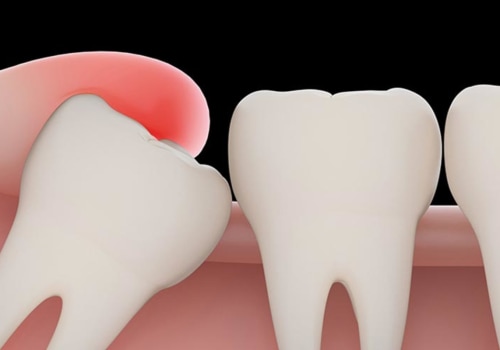

Why Do Emergency Tooth Extraction Procedures Need Dental X-Rays In London

Dental X-rays are an important part of emergency tooth extractions procedure in London. Before tooth extraction, X-rays...

Why Are Dental X-Rays Necessary In Fairview Before Doing Any Dental Procedures

It's a common misconception that dental x-rays are only necessary for patients experiencing pain or other dental...